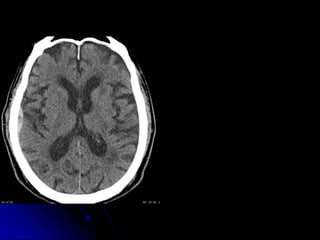

CT PROTOCOLS

• HEAD/CSPINE

• Non contrast

• 1mm acquisition, displayed thicker

• Coronal, sagittal reformats

NON-CONTRAST

C-SPINE IMAGING

ALGORITHM

• CT

• MRI (depending upon Hx, PE, CT

findings)